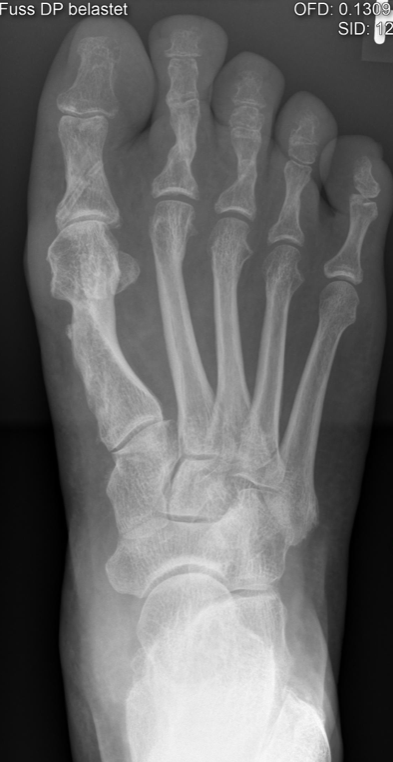

- nach Röntgen Wechsel vom Verbandsschuh in einen geeigneten Konfektionsschuh (Prinzip der steifen Sohle weiterhin zu empfehlen)